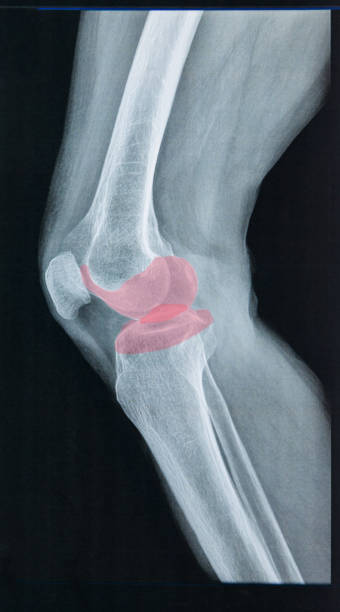

무릎 연골을 정밀 검사하여 찢어진 상태가 좋다는 판단이 선다면 무릎 주변 근력 운동으로 수술을 연기하고 강화하는 것으로 버티는 것이 가능하지만, 파열 전의 상태로 돌아가 반월판 파열된 상태로 살아가야 합니다.

찢어진 연골을 부분적으로 수리하여 원래의 모양으로 회복시키는 치료법도 있는데 얇은 내시경을 삽입하고 미세한 기구로 찢어진 부위를 절제하면서 슬관절의 상태를 관찰하는데 수술 후에는 이틀 정도 재활치료 후 일주일 정도 회복기간을 지나면 일상생활은 가능합니다.

손상이 심해 연골판이 얼마 남지 않아 연골판이 정상적으로 기능하지 못하는 경우 관절염이 생기기 전에 다른 사람의 연골판을 이식할 수 있는데 쉽게 이해하면 각막 이식을 받는다는 행위와 유사하게 타인의 무릎 연골을다. 심장 이식이나 각막 이식 등 사망한 사람에게서 무릎 연골을 채취하여 이식하는 방법입니다. 사람마다 무릎의 크기가 다르기 때문에 자신에게 맞는 크기인지 확인하고, 크기가 비슷하면 연골판 전체를 이식해야 하는데 크게 이식 후 거부반응이 없어 수술로 널리 활용되고 있습니다.

연골을 봉합하는 방법도 있는데 양측 연골판 가장자리의 약 1/3은 혈액으로 재생되어 찢어진 연골을 재생할 수 있지만 내부에 혈관이 없어 부러지면 붙기 어렵기 때문에 혈액이 흐르는 부위의 모양을 찢는 것만으로 봉합할 수 있습니다. 특히 전방십자인대가 동반 손상되는 경우에는 전방십자인대 수술을 하면서 뼈에서 피가 나게 되는데 이 안에 줄기세포가 있어 봉합한 후에 더 잘 붙을 수 있습니다.